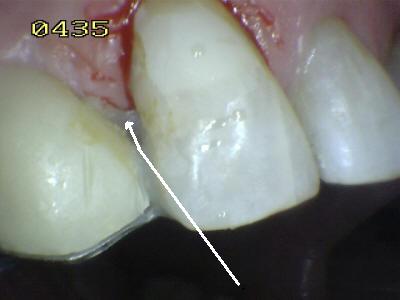

Aspecto vestibular del

r3emanente dentario